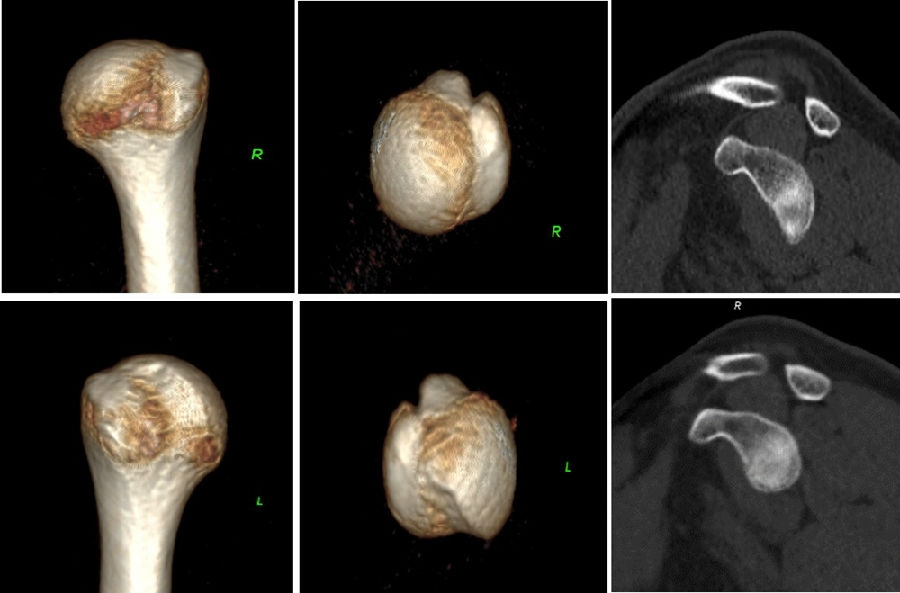

典型病例,苏X,男,36岁。主诉左肩关节反复脱位2年。诊断左肩复发性脱位、左肩胛盂骨折(骨性Bankart损伤)、左肱骨头Hill-Sachs损伤。

手术方案:左肩关节镜下探查清理、Latarjet术。

图45 CT D=26mm d=8mm(上患侧,下健侧)

图46 CT d/D=30.7% GT=0.83D-d=13.6mm Hill-Sachs损伤I级,骨缺损 >25%